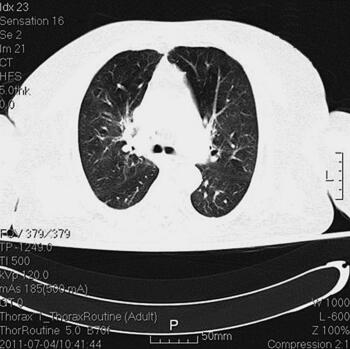

体格检查:P 85次/分,R 12次/分(机械通气),BP 121/61mmHg(多巴胺针剂维持下),T 37.3℃,SPO2 98%。神志清,精神差,气管居中,口插管在位,机械通气,颈静脉无怒张,桶状胸,两肺呼吸音粗,可闻及大量湿啰音及干啰音,心率85次/分,窦性,律齐,双下肢无明显水肿。辅助检查:胸部CT(6月28日)(图1):两肺感染性病变,两下肺支气管扩张症伴感染。心电图(6月28日):窦性心律,T波改变。血常规(6月28日):WBC 13.5×109/L,N 66.3%,Hb 145g/L;CRP(6月28日)3.8mg/L,PCT(6月28日)5.49ng/ml。

图1 胸部CT(6月28日):两肺感染性病变,两下肺支气管扩张症伴感染

诊治经过:入院后留置右锁骨下深静脉导管,监测CVP。患者血压逐渐平稳,停用多巴胺。继续机械通气,头孢哌酮-舒巴坦钠针剂及阿奇霉素针剂联合抗感染,甲泼尼龙及多索茶碱解痉平喘,改善微循环,化痰等对症支持治疗。并予肠内营养,胰岛素微泵控制血糖。复查胸部CT(7月4日)(图2),感染较前明显吸收;复查(7月4日)CRP 10mg/L,PCT 0.22ng/ml。

图2 胸部CT(7月4日),感染较前明显吸收